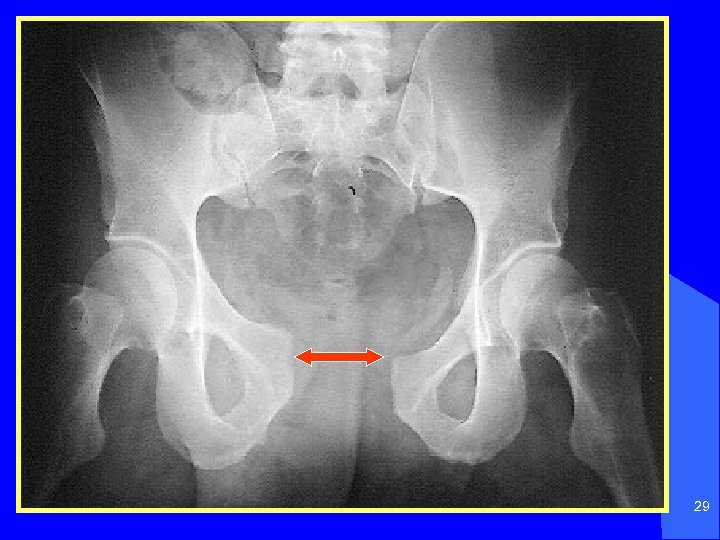

29